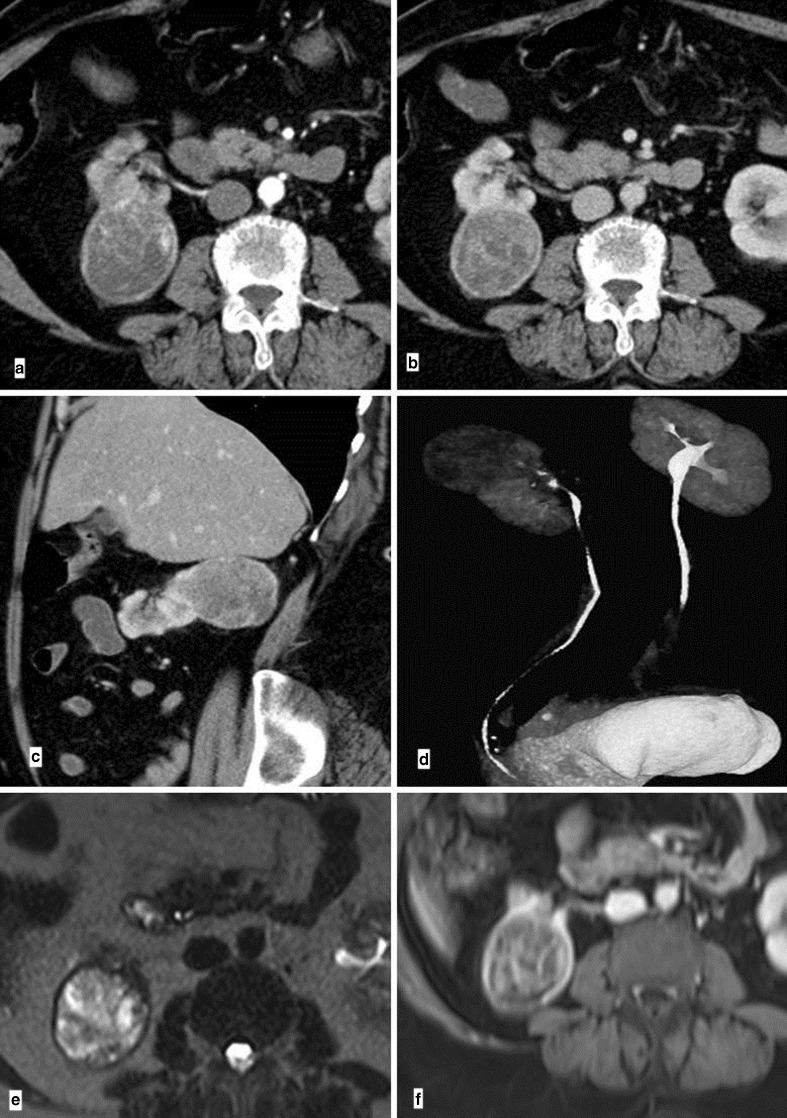

Computed tomography (Fig. 1a–d) showed a well-defined exophytic mass in the upper pole of the right kidney, 5.3 × 4.8 × 4.9 cm, with no obvious perilesional fat stranding. Mass was indenting upon psoas and liver but the fat planes were intact. There was no venous thrombus nor any other intra-abdominal masses or nodes. Whole body magnetic resonance imaging showed a heterogeneous lesion of 5.21 × 4.68 × 5.11 cm at superior pole of right kidney, separate from the right adrenal. The lesion was hyperintense on T2w images (Fig.1e), hypointense on T1w images (Fig.1f). Mass showed intense enhancement on arterial phase and persistent enhancement on venous and portal phases. Fat planes and inferior vena cava were normal. No other lesions were seen anywhere in the body.

Fig. 1.

Contrast-enhanced computed tomography (a, b, c, d) showing well-defined exophytic mass in the upper pole of the right kidney, intact fat planes, and no venous thrombus. Magnetic resonance images showing heterogeneous lesion at the superior pole of the right kidney; hyperintense on T2w images (e) and hypointense on T1w images (f), fat planes are normal and no venous thrombosis